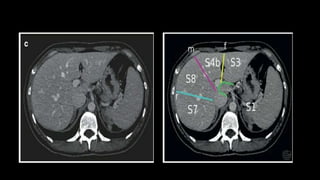

SEGMENTAL ANATOMY OF LIVER

• The French surgeon and anatomist Claude Couinaud divided the liver

into eight functionally independent segments

• allows resection of segments without damaging other segments.

• Each segment has its own vascular inflow, outflow and biliary

drainage.

• In the centre of each segment there is a branch of the portal vein,

hepatic artery and bile duct.

• In the periphery of each segment there is vascular outflow through

the hepatic veins.

• Liver is divided into a functional

left and right liver by a main

scissurae containing the middle

hepatic vein.

• This is known as Cantlie's line.

• Cantlie's line runs from the

middle of the gallbladder fossa

anteriorly to the inferior vena

cava posteriorly.

• Right hepatic vein divides the

right lobe into anterior and

posterior segments.

• Left hepatic vein divides the left

lobe into left medial and left

lateral sections.

• The portal vein divides the liver

horizontally into upper and lower

segments.

• There are eight liver segments.

• Segment IV is divided into segment IVa and IVb according to Bismuth.

• The numbering of the segments is in a clockwise manner.

• Segment I (the caudate lobe) is located posteriorly.

• It is not visible on a frontal view.